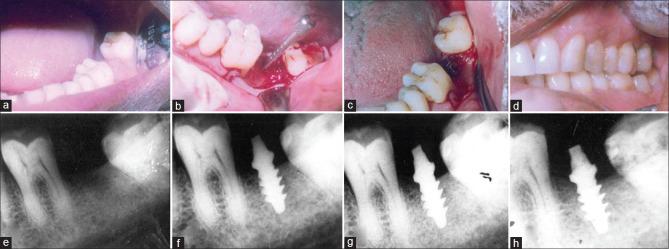

The aim of this study was to report the outcome of single-piece implant-prosthetic complex with a novel cervical platform design in the anterior and posterior jaws 3 years after loading.

The present study included placement of 90 single-piece implants in the anterior and the posterior jaws in varied bone densities. After immediate loading, survival and marginal bone loss was recorded at regular intervals.

Three years after loading, single-piece implants with the novel cervical platform design provided survival rates of 93% in the maxillary anteriors and 91% in the mandibular posteriors. D3 bone showed more marginal bone loss than D2 bone.